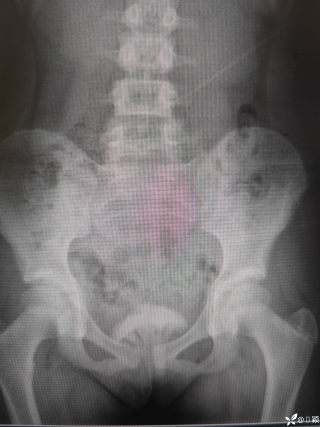

文/西地兰 特别声明:所有观点仅代表个人言论 特别声明:与当事双方均无利益相关 山东男孩,目前全网沸沸扬扬,看过一些观点,直言不讳地说,大多偏颇。要么一股脑地指责医方的全责,甚至有说千万别在县医院看病。要么又为医方无休止的遮羞,认为这样的手术在县医院做下来已经非常了不起。而我想到的是,以后面临类似的病例,我们怎么办?那么我们不如来一次专业的病案讨论。既然是事后讨论,难免有事后诸葛亮的感觉,但是假如下一次,同行们遭遇这样的病例,如何处置?这是医疗行业所面临的问题。希望我整理的这些思路和相关病例,对同行们有所帮助!就目前的资讯外界不足以判断是否需要急诊,如果需要急诊,那么只能根据术中所见进行处理,

目前知道的消息,第一,术前发现一个血肿,然后做增强CT发现一个占位,没说血肿与肿瘤的关系,术后病理没有描述肿瘤出现破裂出血,大概率就一个小血肿,我就不明白当地主任凭哪个指针去给这小孩开急诊刀的?哪个指南告诉他需要急诊开?第二,诊断不明确他想的不是进一步检查,一边观察一边进一步查,他反而选择腹腔镜探查,这个探查的指针在哪?第三,腹腔一个血肿,没有活动性出血,没有血压心率出现问题,为什么要开腹进去碰它?不能等血肿吸收再明确肿瘤性质吗?第四,1点进腹,3点病理结果出来,按这个时间还算顺利,应该还没出事,孩子还算平稳,病理是低度恶性,切了就治愈,他一年能开几台这手术,就敢继续做,拿孩子练手。第五,后面

2023年10月26日,来自山东菏泽市成武县的小烨和他家人的命运被彻底改变了。这个原本阳光、可爱的小男孩在一次意外被撞击后,在医院检查出了腹腔内存在肿瘤,并在手术中被切除了包括十二指肠、胰腺、大部分胃和小肠等多个器官。此后便无法再像正常人一样吃饭、喝水,活着要靠长期静脉注射营养液。一份2024年12月由第三方机构出具的司法鉴定意见书显示,当时给小烨做手术的成武县人民医院在该医疗行为中存在过错,与小烨的损害后果之间存在因果关系,建议医疗过错在损害后果中的原因力大小为同等原因。此外,另一份由成武县卫生健康局在2025年9月28日发出的书面答复中显示,成武县人民医院存在24小时内未完成病历;手术知情